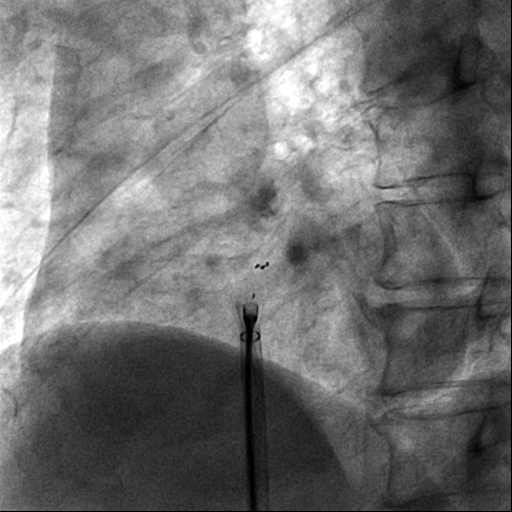

但是可降解封堵器无金属支架,可塑性和顺应性均较传统的金属封堵器要弱,增加了手术的难度,且封堵器在X线下不能完全显影,对于手术的引导手段提出了更苛刻的要求,目前多数医院采用经食管超声引导,这就需要全程麻醉,增加了手术风险和病人的痛苦,团队经过术前反复讨论,为其量身定制了目前更安全和可靠的四点标记的可降解封堵器应用X线及经胸心超的极简式引导手术方案。手术顺利进行,术中心房造影和术后心超均显示卵圆孔彻底闭合,无残余分流。术后第三天患者顺利出院。